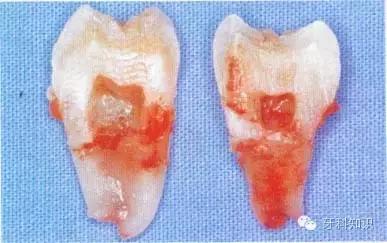

3.拔除患牙:将牙钳喙准确放置于患牙的唇舌侧或颊舌侧,使钳喙与牙齿长轴方向缓慢摇动,随着牙齿松动度增大,用力向外牵引拔出(图5-10,图5-11)。

单根牙牙根呈锥形者

,可以稍加旋转力量拔出。

单根牙牙根呈扁平状者(如

)和多根牙,应避免旋转力,并宜顺着牙根弯曲的方向拔出,否则易折断牙根。